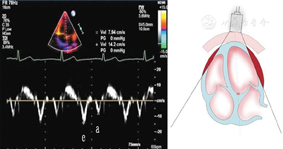

标准心尖四腔切面和两腔切面引导采用Simpson双平面法进行左心室舒张末期和收缩末期容量测量方法,采用同步心电图确定准确舒张末期和收缩末期时相